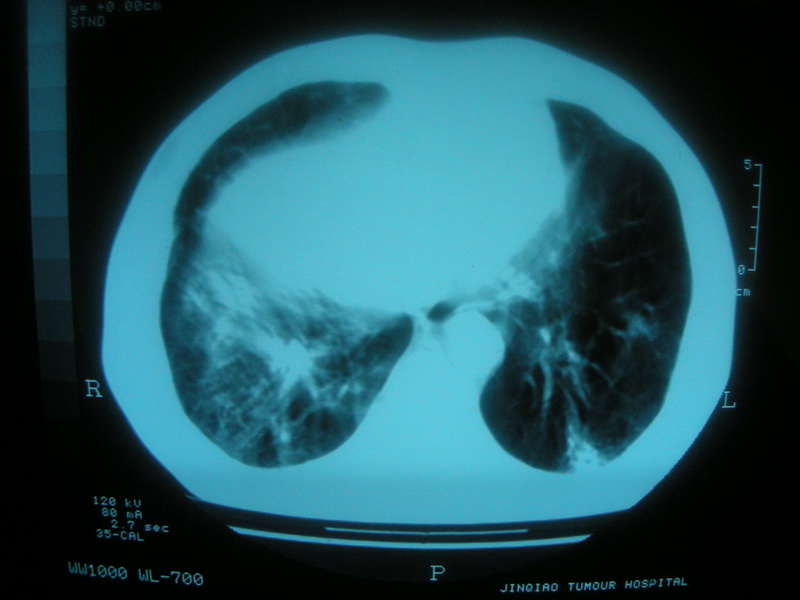

标题: CT11692:男,63岁,糖尿病史15年.抗炎治疗7天,病情 [打印本页]

标题: CT11692:男,63岁,糖尿病史15年.抗炎治疗7天,病情

请老师看看是结核还是炎症?

根据影像表现及临床符合结核感染。

双肺继发性肺结核伴感染!

双肺继发性肺结核伴支气管播散。

糖尿病首先考虑结核并感染。